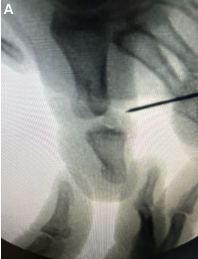

Irreducible Dislocation of the Great Toe Interphalangeal Joint Secondary to an Incarcerated Sesamoid: A Retrospective Case Series of Six Patients

Salman Durrani , Navneet Goel , Juvesh Kumar , Nischay Kaushik , Apoorv Dua , Abdul Sattar

………………………………p.381-387